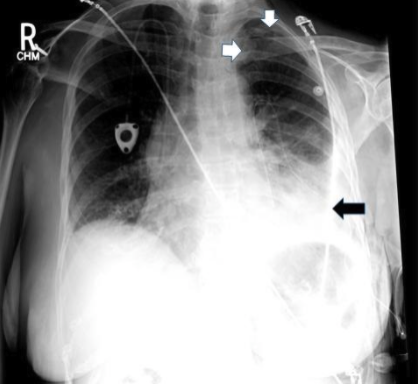

10/ With large pleural effusions, you typically get a contralateral shift of the mediastinum. However, with lung entrapment you will typically see the mediastinum shift ipsilaterally of the effusion or no shift at all. @CritCareMed @PulmCrit @MedEdPGH @gradydoctor